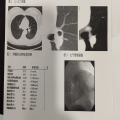

| 影像学检查:(点击查看大图) | 2025年12月5日住院肺CT提示:“左肺上叶支气管腔内见类圆形小结节影,长径约7mm,CT值约45HU,远端支气管显示,增强后可见强化。右肺上叶后段、右肺水平裂见实性结节。左肺下叶少许条索影。两肺门区未见异常密度影。![]() |